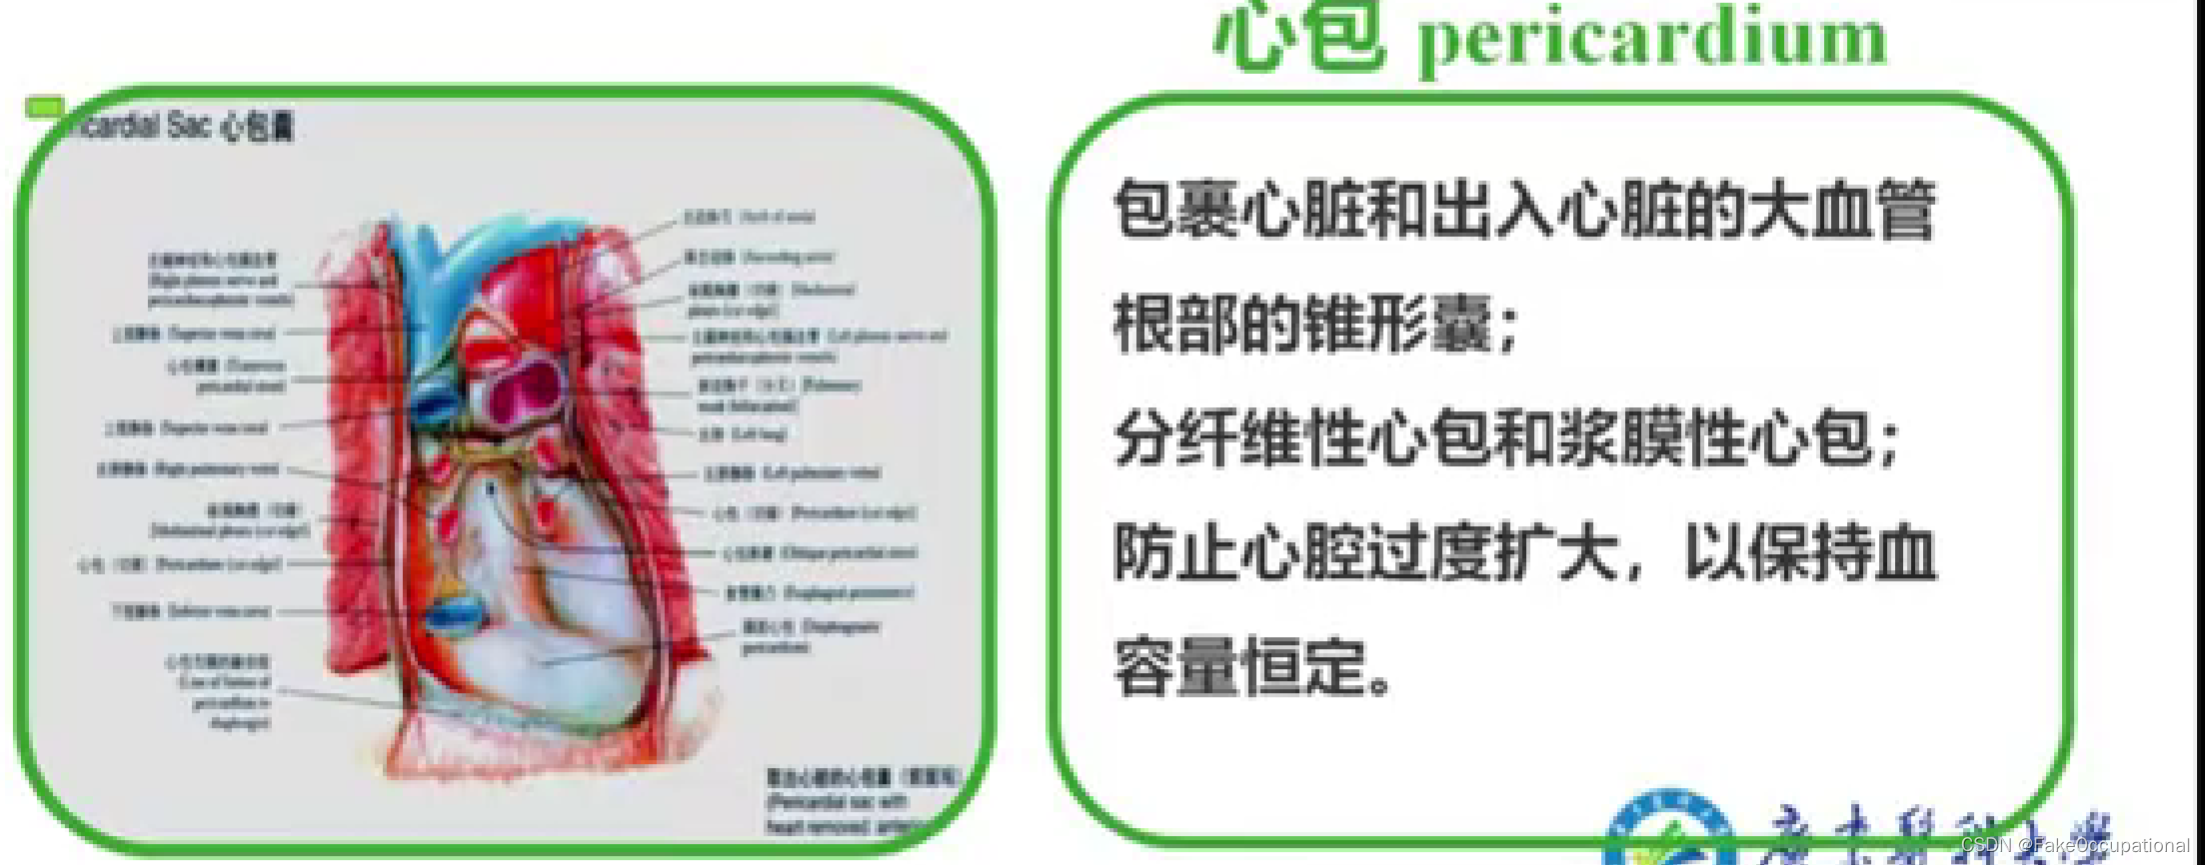

心脏解剖及生理概要